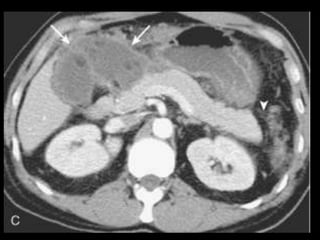

Pancreatite Crônica

TC: dilatação e estreitamentos ductais irregulares,

atrofia do parênquima e calcificações pancreáticas;

Dilatação é frequente, mas não é específica:

carcinomas pancreáticos e ampulares;

Um ducto uniforme e dilatado, com uma razão do

diâmetro do ducto para o diâmetro total da

glândula superior a 0,5 é sugestivo de carcinoma.

Cálculos ou calcificações pancreáticas são as

manifestações na TC mais específicas da PC e não

se encontram em associação à obstrução

neoplásica.

Embora a história clínica, calcificações na massa,

cálculos ductais e ramos laterais ductais dilatados

possam ajudar a diferenciar as massas benignas

das malignas, isso pode não ocorrer sempre,

porque uma pancreatite obstrutiva aguda e crônica

pode preceder um carcinoma demonstrável;